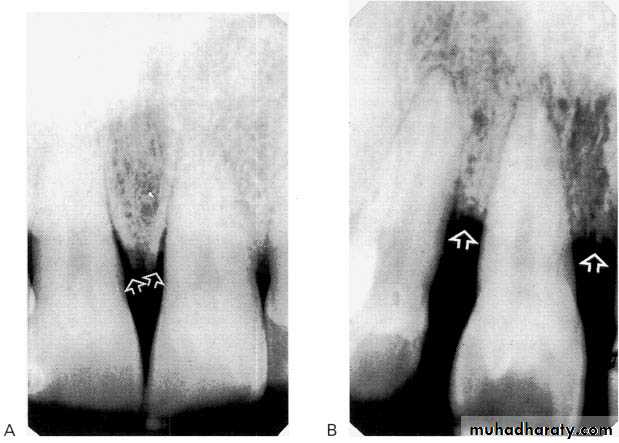

The normal alveolar crest lies 1 to 1.5 mm below the adjacent CEJs and forms a sharp angle with the lamina dura of the

adjacent tooth.

Between the anterior teeth the alveolar crest normally is pointed and well corticated.

1. Horizontal bone loss:- When loss occurs on a plane that is parallel with a line drown.

2.Vertical bone loss:- when there is greater bone loss in one tooth than on the adjacent tooth, so the bone level is not parallel with a line joining the CEJ.